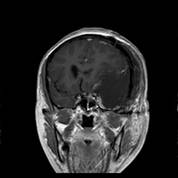

术前MRI可见左侧额颞巨大占位,增强均匀强化,考虑脑膜瘤

术后复查MRI可见肿瘤全切